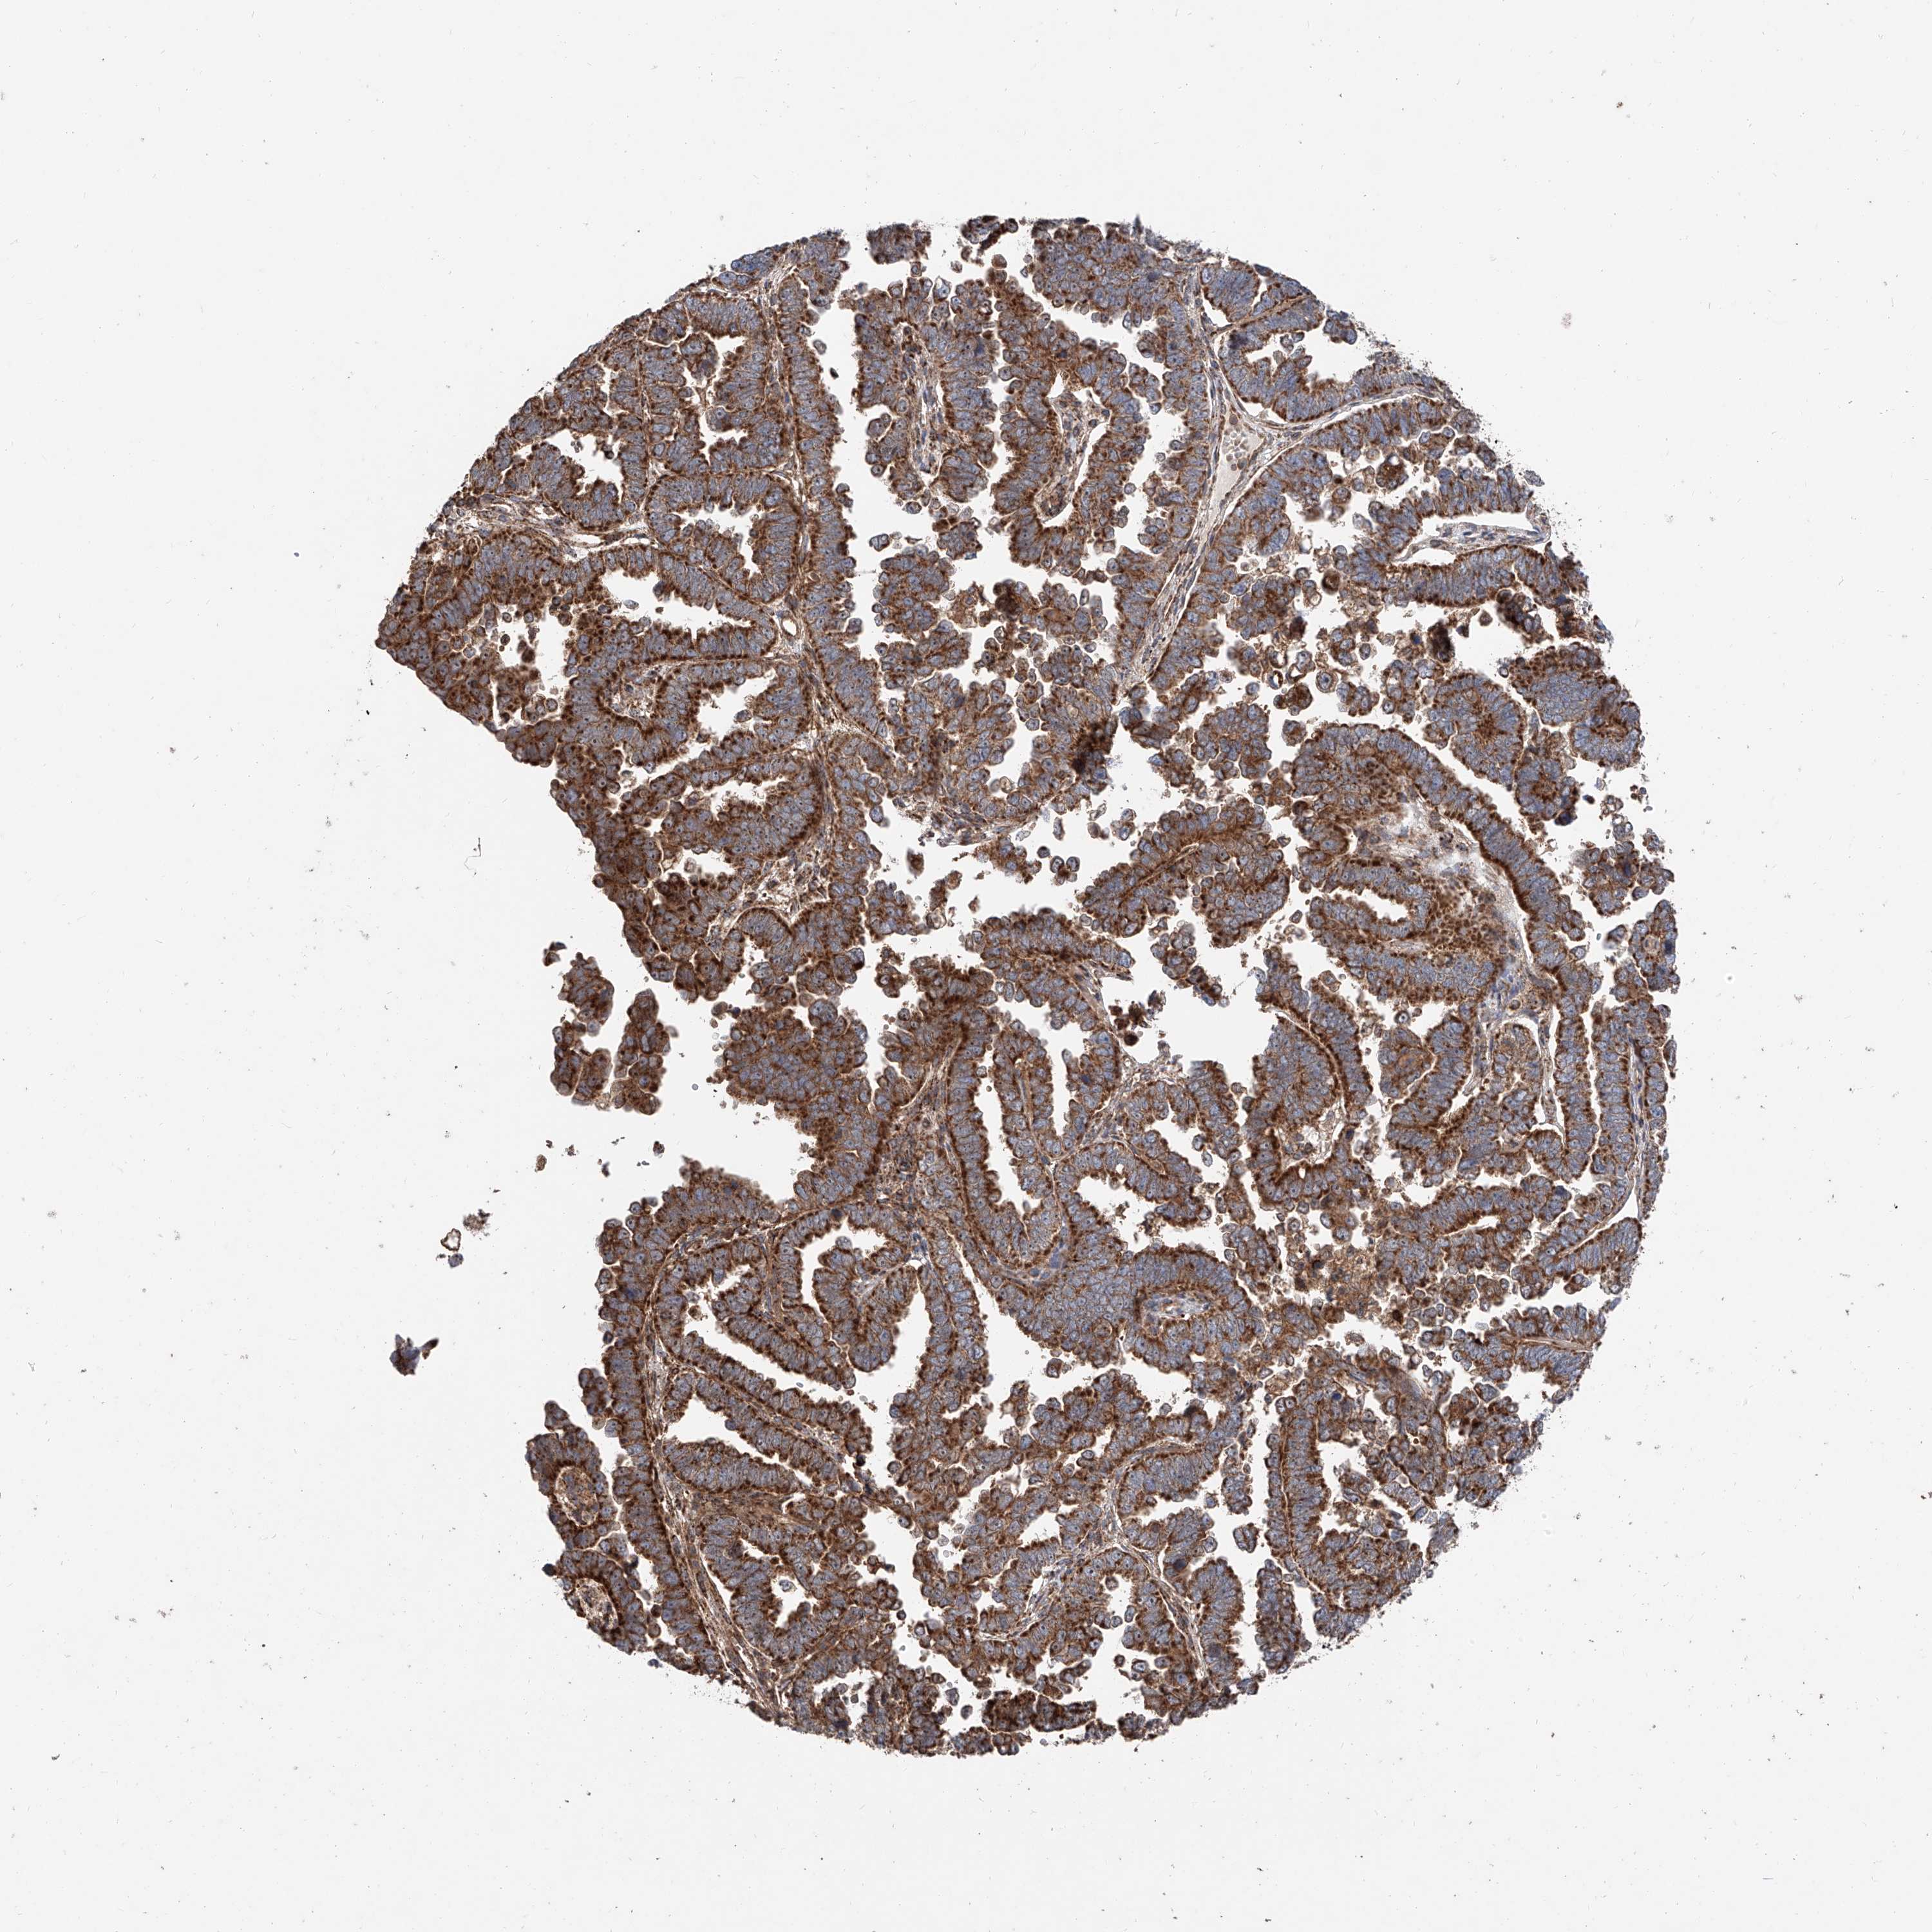

ENDOMETRIAL CANCER - Protein expressioni

A mouse-over function shows sample information and annotation data. Click on an image to view it in a full screen mode. Samples can be filtered based on level of antibody staining by selecting one or several of the following categories: high, medium, low and not detected. The assay and annotation is described here.

Note that samples used for immunohistochemistry by the Human Protein Atlas do not correspond to samples in the TCGA dataset.

Antibody stainingi

Antibody staining in the annotated cell types in the current human tissue is reported as not detected, low, medium, or high, based on conventional immunohistochemistry profiling in selected tissues. This score is based on the combination of the staining intensity and fraction of stained cells.

Each image is clickable and will lead to virtual microscopy that enables deeper exploration of all samples and also displays staining intensity scores, fraction scores and subcellular localization as well as patient and tissue information for each sample.

Antibody HPA031090

Antibody HPA031091

Staining

High

Medium

Low

Not detected

Intensity

Strong

Moderate

Weak

Negative

Quantity

>75%

75%-25%

<25%

None

Location

Nuclear

Cytoplasmic/membranous

Cytoplasmic/membranous,nuclear

Adenocarcinoma, NOS